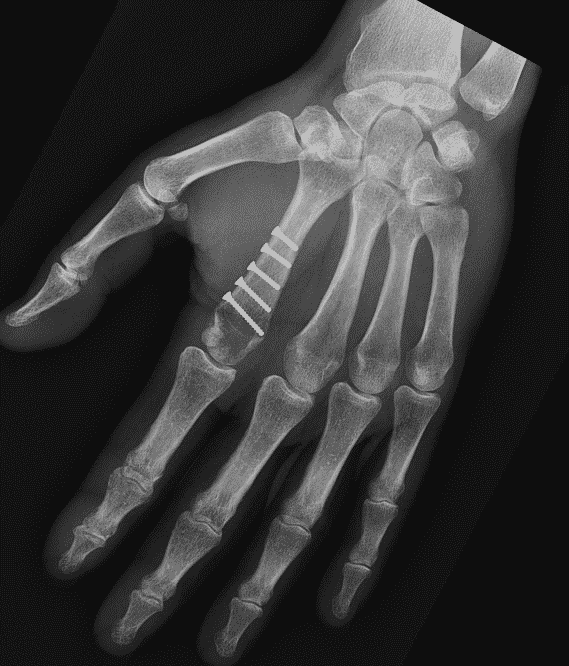

Les fractures du col métacarpien relèvent le plus souvent d'un embrochage de type "Foucher". Le chirurgien introduit des broches dans l'os par sa base. A l'extrémité de l'os les broches vont maintenir le col fracturé.

On retire les broches vers la sixième semaine. En attendant on immobilise le doigt atteint ainsi que son voisin par une attelle "intrinsèque plus".